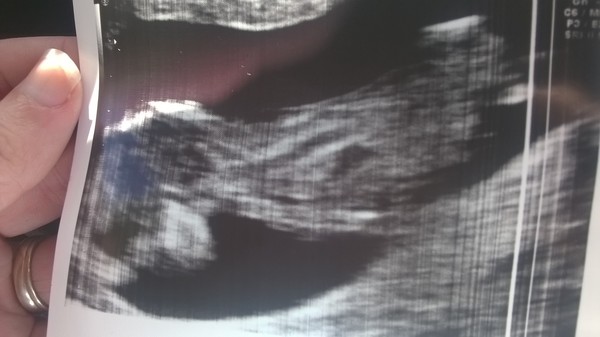

So.... I have another introduction to make to the thread. Most people seem to have a lovely looking baby laying on their back during scans. Mine wasn't having any of it and refused to move despite being sent away and coming back for a second scan. So I have a comical looking picture of my baby in a sky diving pose. All healthy and fine - I cried so much!!

Sorry - I should have said congrats Carrick - that is a lovely pic!!